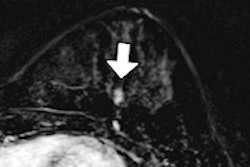

They retrospectively evaluated the software, which is designed to identify both masses and microcalcification clusters, on a test set of 143 cases. The 143 patients received craniocaudal (CC) and mediolateral-oblique (MLO) DBT projections on a Selenia Dimensions full-field digital mammography system (Hologic), generating 484 breast volumes. The DBT projections were reconstructed using the Briona tomosynthesis 3D image reconstruction software library (Real Time Tomography) prior to receiving CAD.

The 143 cases included 84 biopsy-proven malignant lesions with a mean size of 23 mm (standard deviation = 18 mm). These 84 malignant lesions included 59 masses or architectural disorders, 19 microcalcification clusters, and six masses with associated microcalcifications. There were 64 benign lesions (proved with biopsy or follow-up) with a mean size of 18 mm (standard deviation = 14 mm).